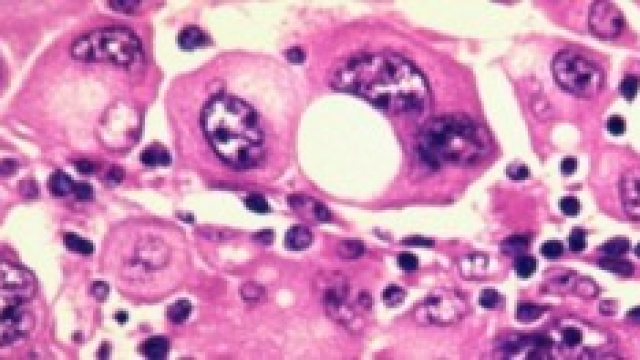

Come ben saprete la particolarità maggiormente devastante del tumore sono le metastasi, che non sono altro che cellule che si separano dalla massa primitiva tumorale e vanno ad intaccare tutto l'organismo causando il manifestarsi di altre e numerose neoplasie. La sola cura attualmente messa in atto è la chemioterapia, un processo con pesanti controindicazioni per l'organismo e che nella fase terminale del cancro metastatico non risulta essere abbastanza aggressiva da combatterlo. La proteina bioingegnerizzata non annienta le cellule tumorali, bensì ferma l'avanzamento delle molecole responsabili della formazione della metastasi.